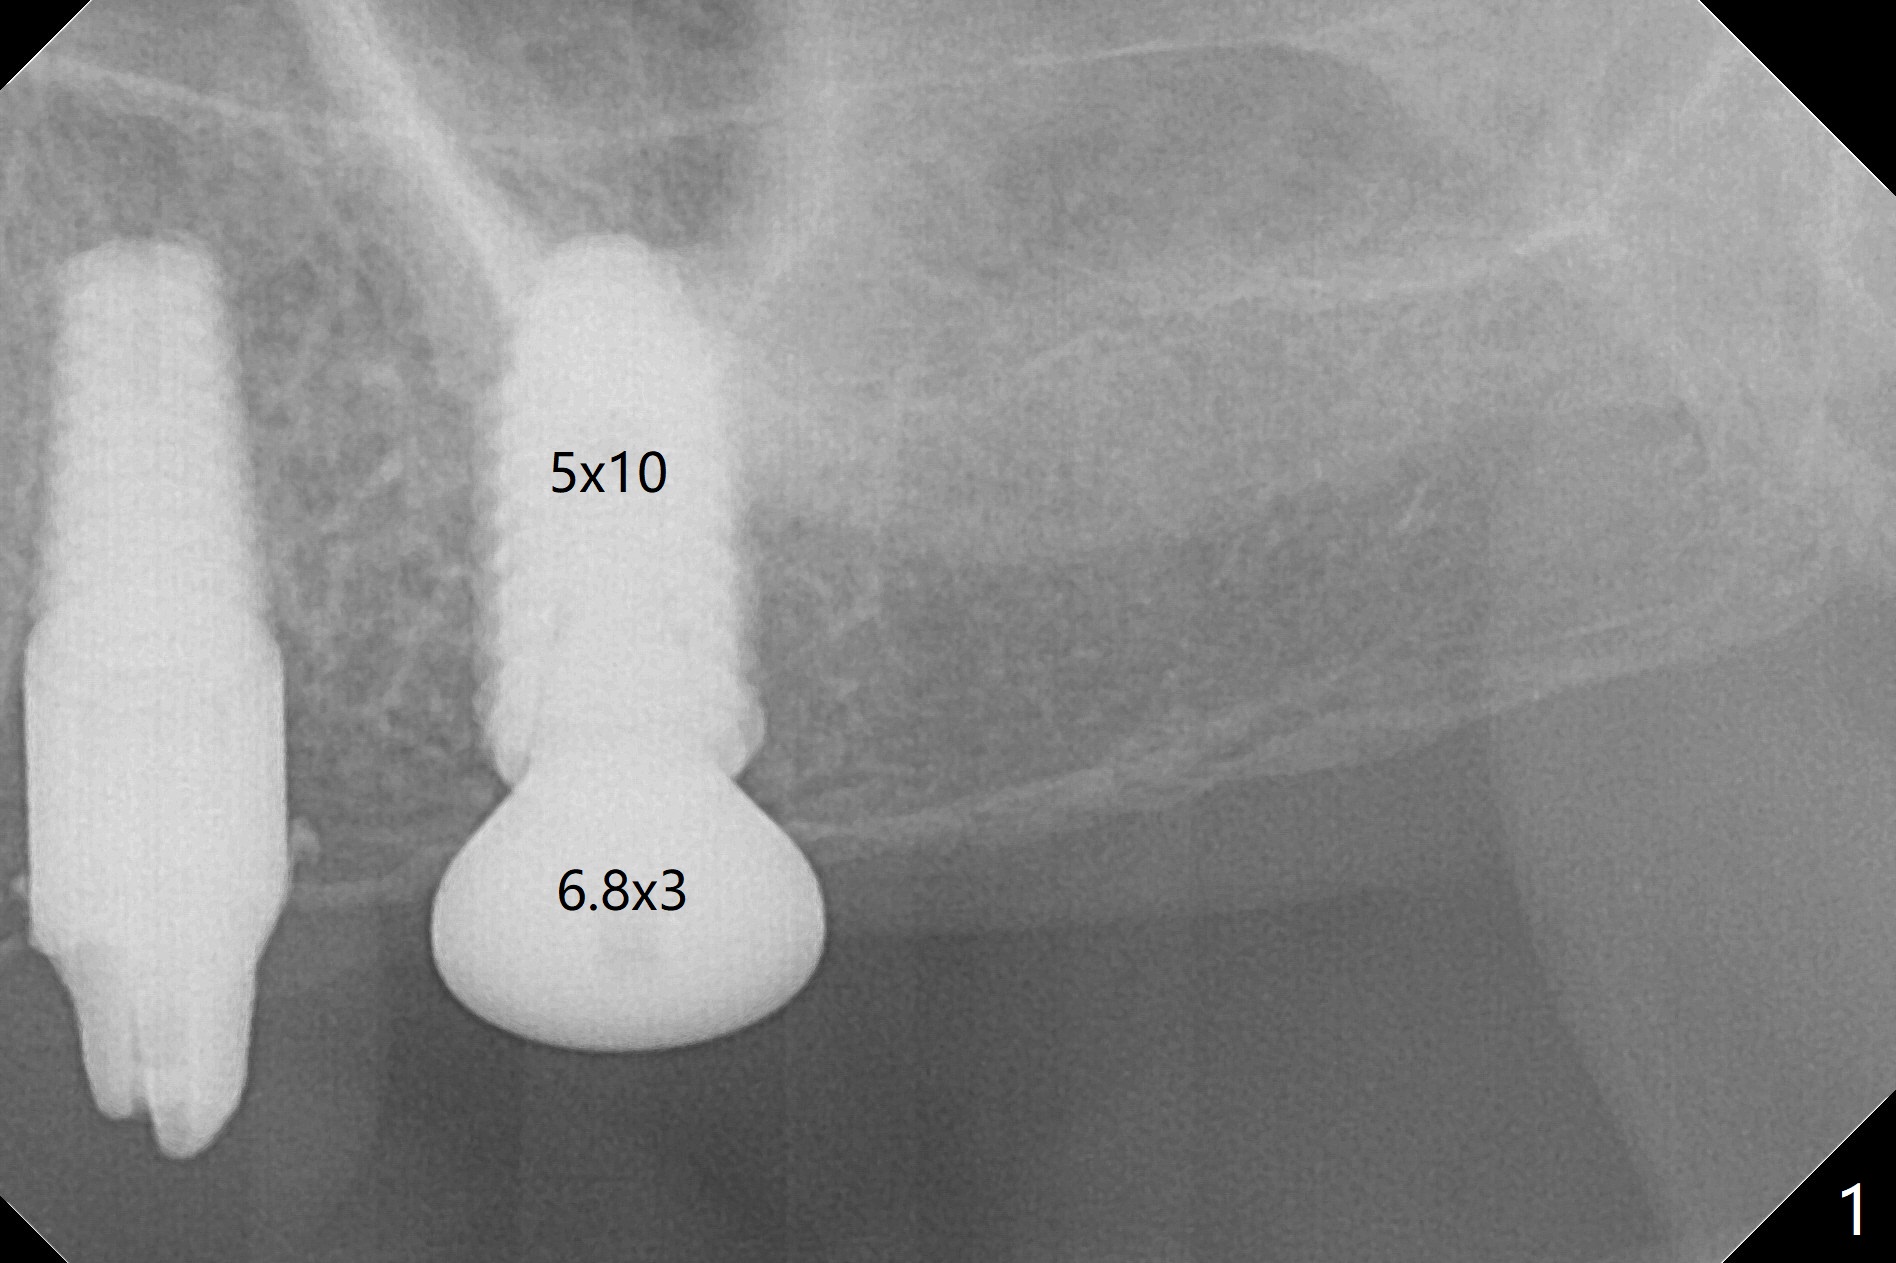

M

As a surgeon, I have never felt that my scalpel is as precise as media claims to be until guided surgery is introduced. The implants at #14 and 19 are placed as precisely as planned as well as painlessly and quickly (Fig.1-4). What else can we ask for? The gingiva around the healing abutment (5.5x3 mm) at #19 is erythematous (Fig.5). Later a longer healing abutment is used (Fig.6 (5.5x5 mm)). There is no bone loss 5 months or 7 months postop (Fig.6-9). The abutment screw is loose 3 months post cementation due to unfavorable crown/implant ratio (Fig.10); in fact the abutment is incompletely seated. Bicon implants will be in consideration to reduce screw loosening if implants are to be placed at #15 and 18. The abutment screw at #14 becomes loose 10 months post cementation; after retorque at #30 Ncm, the abutment is incompletely seated (Fig.11). It remains the same after use of 4.6 and 5.6 mm profile drills (Fig.12). A healing abutment is placed. When the patient returns, use planning kit and try to place a 5.2x5.5(2) cemented abutment. In fact it works (Fig.13). The crown at #19 is loose again 1 year 5 months post retightening. After removing crown/abutment, the mesial surface of the crown is heavily reduced. The crown/abutment is reseated to make sure that there is no proximal contact between the neighboring teeth (Fig.14 arrow). Because of tilt of the PA, it is difficult to tell the tightness of the contact between the implant and abutment, but the apical space is significantly reduced (*, as compared to Fig.10). Pick up impression is taken for porcelain addition occlusomesially. Two months later the patient returns for crown recementation. When the abutment is reseated with the repaired crown, the seating is incomplete (Fig.15). The abutment is completely seated when it is turned free hand with the flat surface of the abutment faces distal (Fig.16 D). The screw is torqued 20 Ncm before reimpression.